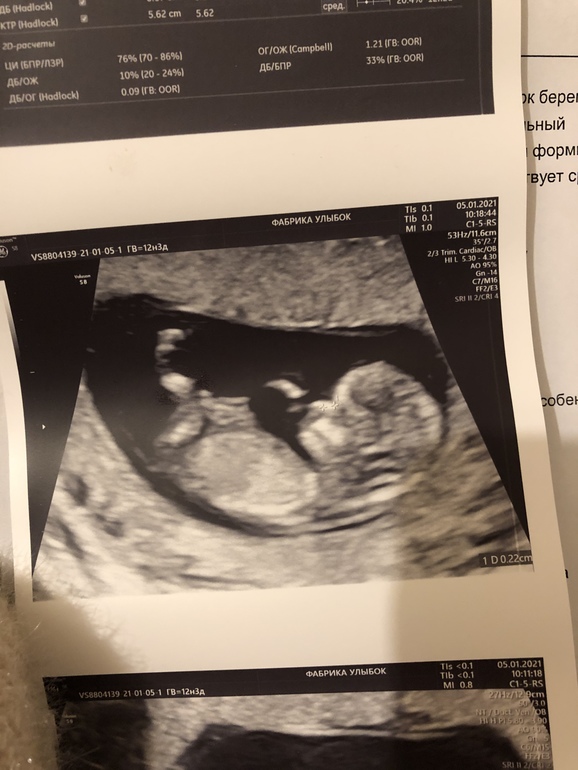

Мужчинка! Мой мужчинка!!!! Правду говорят, что мальчики на узи не прячут свои 🍒

УЗИ, КТГ, доплерЕщё до НГ, по Нипс, я узнала что, таки, выпросила у Боженьки сыночка 💕

На скрининге платном у доктора, которому доверяю, сомнений тоже не возникло - уверено разглядела парня.

На бесплатном скрининге тоже увидели мою ягодку-малинку !

По поводу УЗИ. На первом скрине не предполагали даже... Хотя срок был 12+4.на втором чётко сказали мальчик. Я не поверила ушам🤣🤣🤣и была на 7ом небе от счастья. Получилось все так, как я и хотела. Две дочки и сыночек💞

Мне тоже так Узистка сказала на 13,2 недели, что мальчики достоинство выставляют.